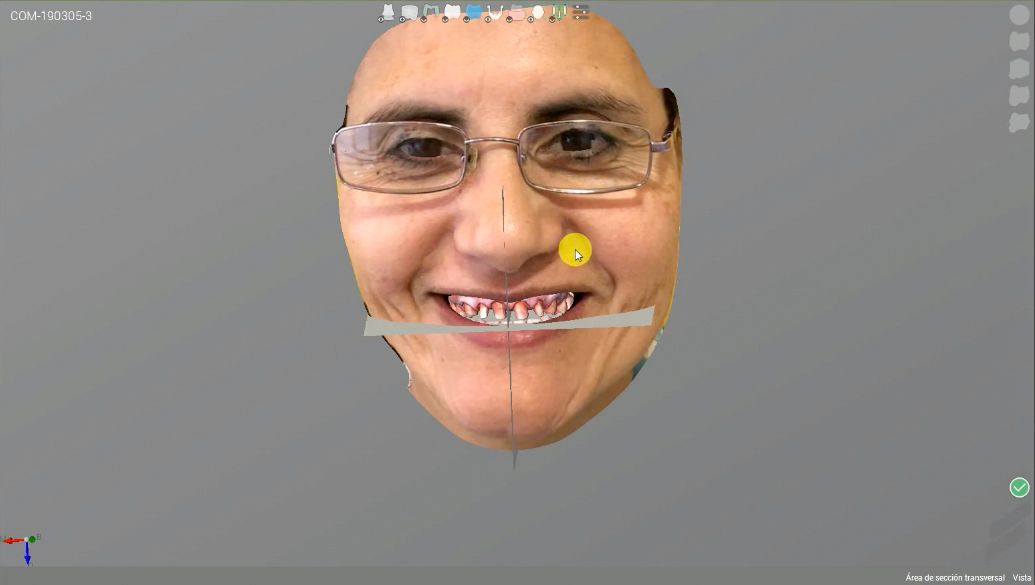

After a further intraoral scan, a new smile was designed using Straumann CARES® Visual. A 3D model printed with the Straumann P30 3D printer was used for the digital wax-up. Pictures were taken to register all the details needed for the final design of the restorations.

At the next appointment, the patient came to the clinic early in the morning. All old crowns were removed, and teeth 24, 25 and 34 were prepared for crowns. Intraoral data were acquired with the new Straumann Virtuo Vivo™ intraoral scanner, and a picture of the patient’s face was taken.

STL files of the digital wax-up, teeth preps, and the patient’s picture were uploaded to the Straumann CARES® Visual software, and crowns were designed. After 25 minutes, all the crowns were sent to be milled with the Straumann C series milling machine. On completion of the milling process, all the crowns were placed for a final fit check (Figs. 9-13).